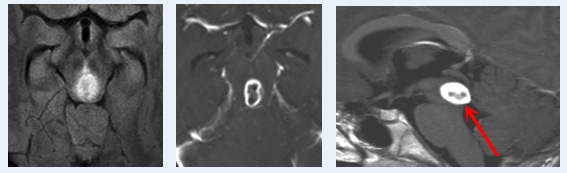

术前MRI

“这个病例的特殊性在于,”巴教授分析道,“肿瘤可能已经向上延伸到第四脑室。如果从小脑上部区域到达第四脑室是非常困难的,由于解剖限制,手术深度很难超过两厘米,这给全切肿瘤带来了巨大挑战。”

但巴教授提出了突破性的解决方案:“通过枕叶方向,我们可以安全切除肿瘤下半部分。或者,可以采用脉络膜下髓帆入路可以直达肿瘤最低部位,这在我的临床实践中已经得到反复验证。”

术后MRI